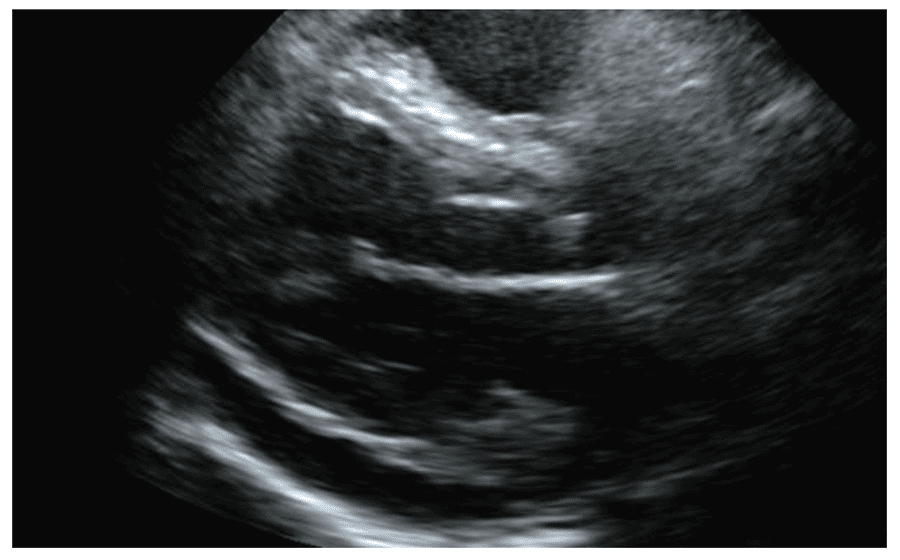

僧帽弁逆流

心嚢液貯留

主な所見

僧帽弁逆流/大動脈弁逆流

心臓の弁が正常に閉まらないことで血液が逆流している状態です。血液の逆流が軽度な場合、症状を自覚することはほぼありませんが、中等度~高度になると息切れや動悸、呼吸困難などがみられることがあります。原因として先天的なものや後天的なものがあり、加齢が原因となることもあります。